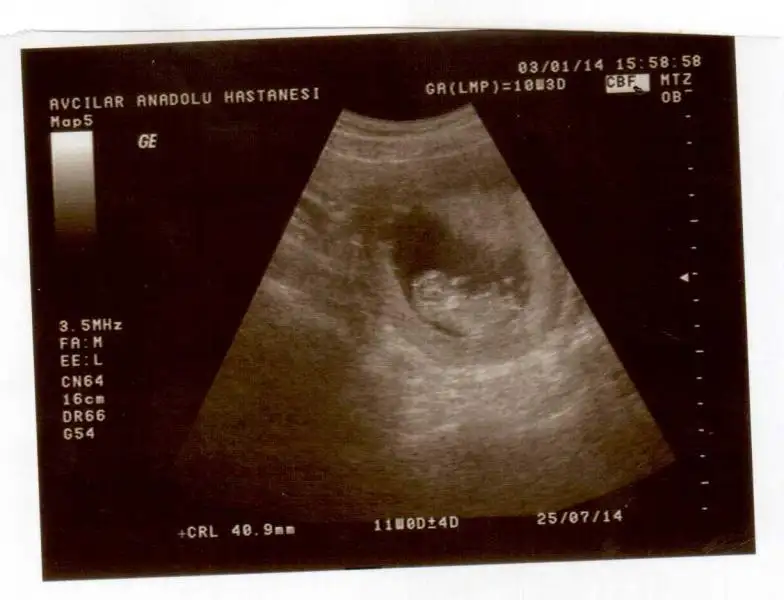

Eki Görüntüle 929354 Eki Görüntüle 929355

Kızlar benim ilk hamileliğim şu an 8. Haftadayım biliyorum çok çok erken fakat bu topiği takip ediyordum sanki cinsiyeti belliymiş gibi geldi. Anlayanlar bana da yorum yapabilir mi merak ettim :)

Eki Görüntüle 926345 Eki Görüntüle 926344 Eki Görüntüle 926346